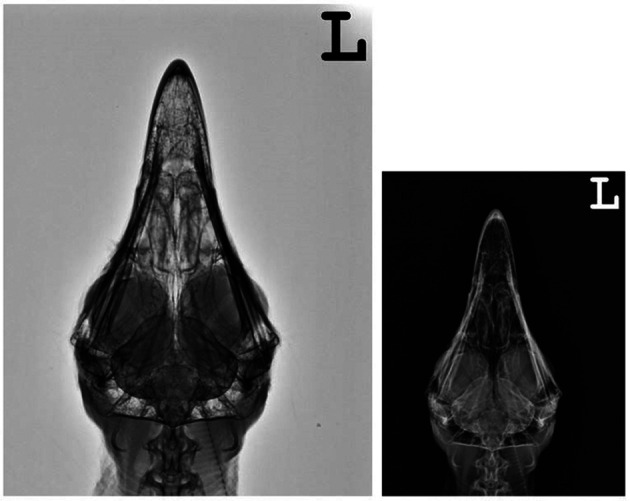

Radiographic appearance of head and eyes

Right lateral (Fig. 7) and ventrodorsal (Fig. 8) skull radiographs showed cranium of cinereous vultures contained many connects to the sinuses. An osseous scleral ring is more visible in radiographs but interlobular septum between both eyes is hardly visible.

Fig. 7.

Lateral xeroradiograph and radiograph of the head of a normal cinereous vulture (Aegypius monachus).

Fig. 8.

Ventrodorsal xeroradiograph and radiograph of the head of a normal cinereous vulture (Aegypius monachus).